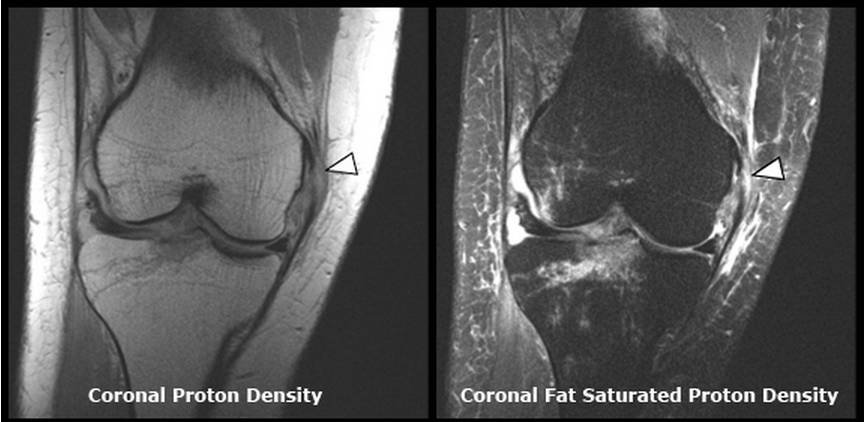

MRI极少用于单纯(或轻度)内侧副韧带损伤的检查,多用于严重内侧副韧带损伤时,体格检查有困难或怀疑其他损伤存在时的内侧副韧带损伤范围的评估及判断其他相关损伤是否存在(前交叉韧带撕裂)。根据MRI表现也可对内侧副韧带损伤按严重程度分为三级,但与临床严重性相关性并不大,由于借助MRI可区分内侧副韧带深层与浅层,因而MRI可能更有益于上述III级损伤的评估。根据MRI的表现决定是否进行手术修复,尤其是当存在内侧副韧带深层的挤压性改变时。

内侧副韧带损伤时MRI的典型表现包括韧带深浅两层间的滑膜囊肿胀、皮下软组织肿胀、内侧副韧带撕裂与周围血肿。韧带纤维的损伤可从单纯的排列紊乱到完全撕裂(图5~图8)。其他MRI表现有关节腔积血、股骨外侧髁或胫骨平台挫伤、半月板损伤、其他韧带损伤、以及股骨内侧髁的部分撕脱骨折(极为少见)。MRI的冠状位图像可很好地观察内侧副韧带及后内侧角。

滑囊炎、骨关节炎、支持带损伤和内侧半月板囊肿的MRI表现与内侧副韧带损伤类似,注意鉴别。